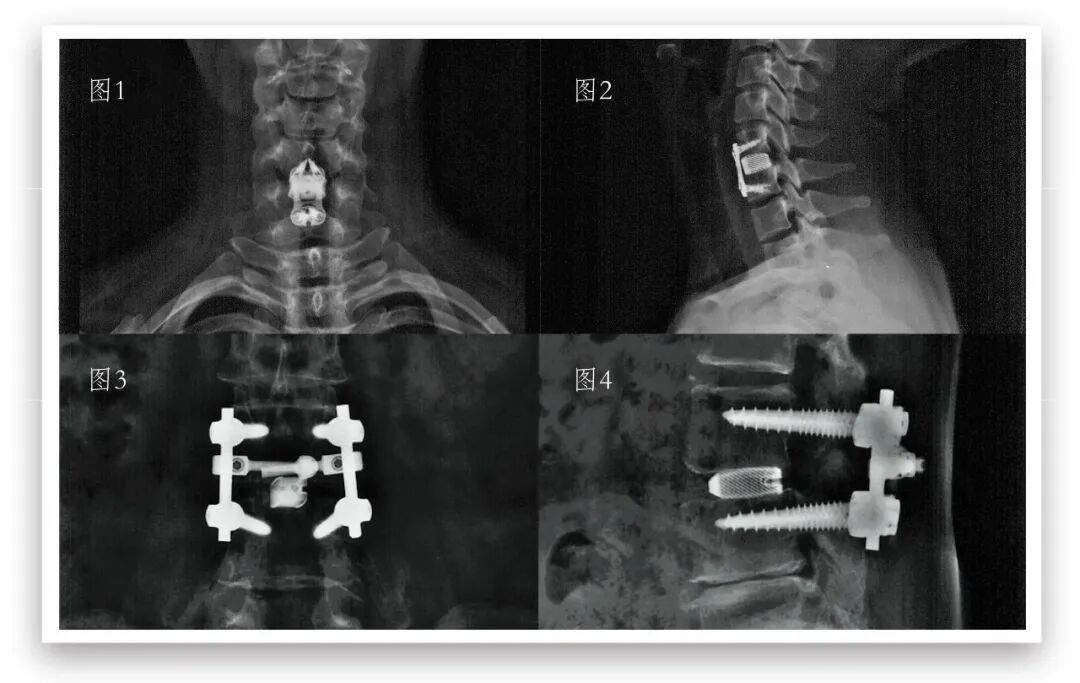

图1:颈椎术后6月—正位    图2:颈椎术后6月—侧位

图3:腰椎术后6月—正位    图4:腰椎术后6月—侧位